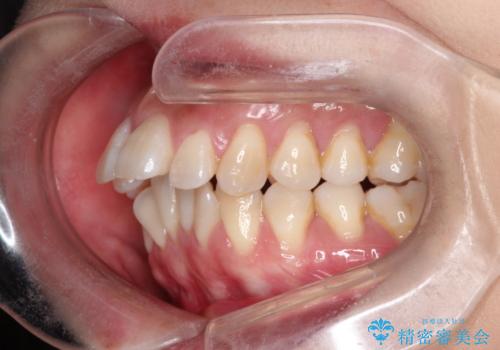

出っ歯で口が閉じずらい ワイヤー抜歯矯正

- 出っ歯がきになるとのことで来院されました。

上顎の前歯は前方に傾斜しており、下あごの前歯にもガタガタがありました。

上下左右の小臼歯を合計4本抜歯して矯正することとしました。